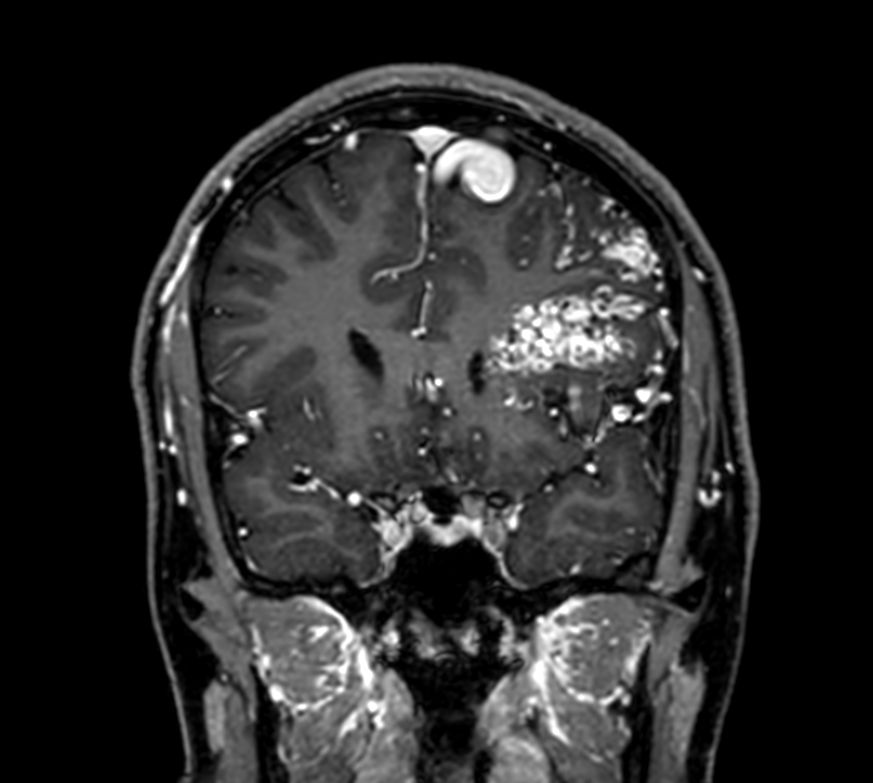

Pediatric brain with AVM

Pediatric patient with frontal brain AVM. MultiVane XD is used to achieve high resolution diagnostic images, even in the case of severe patient motion. SWIp sequence is added to acquire exquisite susceptibility contrast. The 3D sequences with isotropic voxel size enable reformats in any plane without loss of resolution. And 4D-TRAK XD, a fast, dynamic contrast-enhanced MR Angiography method allows to achieve high spatial and temporal resolution simultaneously. Integration of Compressed SENSE acceleration technique enables speeding up of the entire exam.

3D T1w TFE +gado - Coronal reformatCompressed SENSE